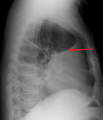

Massive left-sided pleural effusion (whiteness) in a patient presenting with lung cancer.

A pleural effusion as seen on lateral upright chest x ray